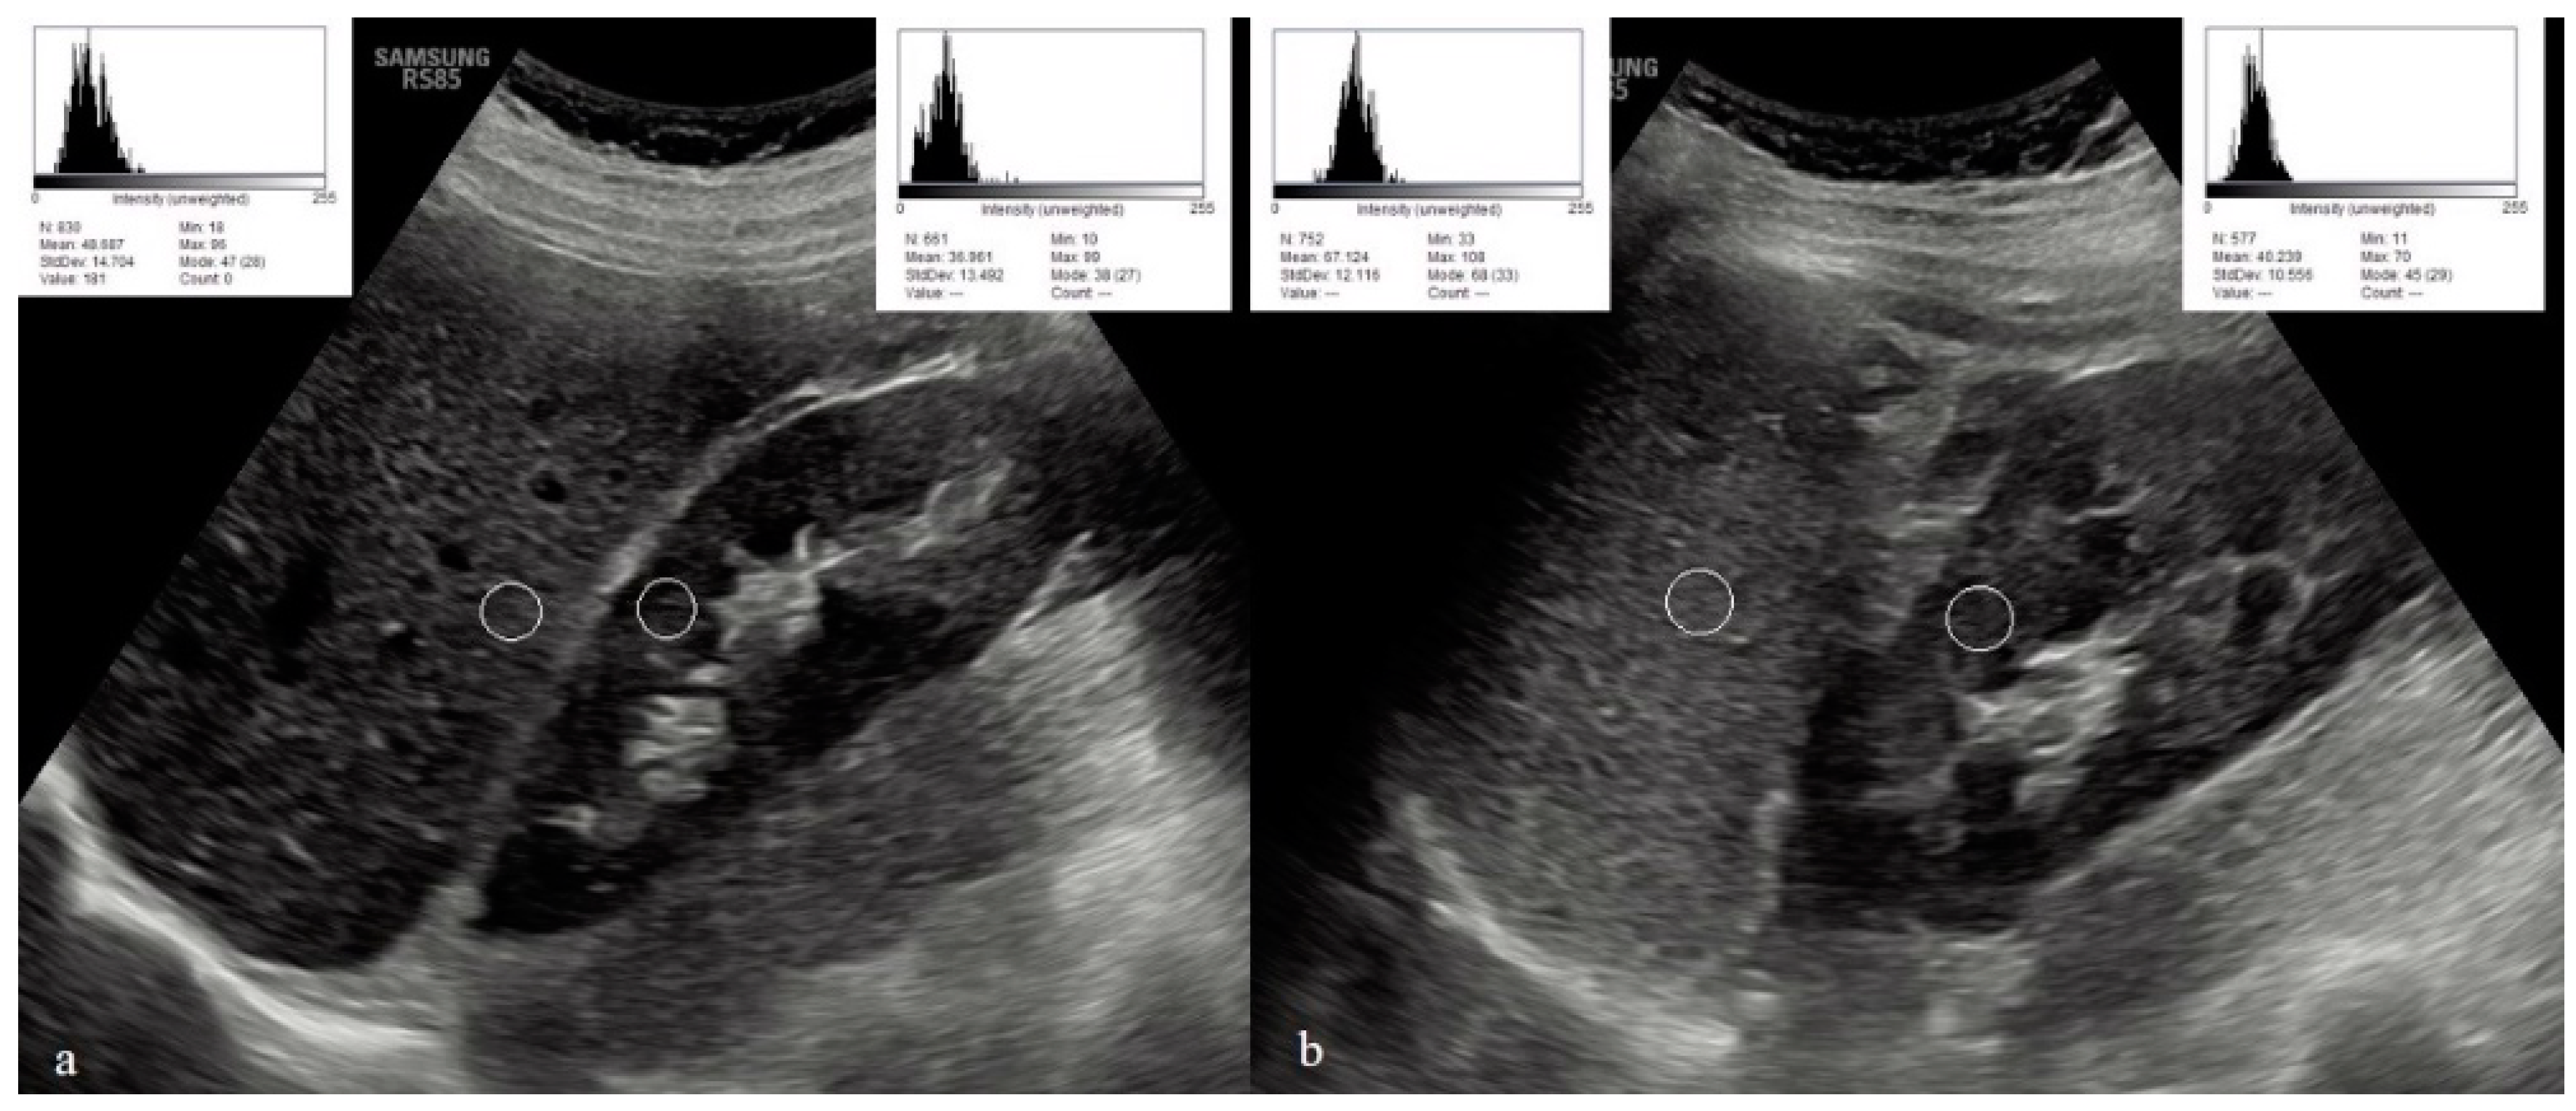

To evaluate the US hepatic/renal (HR) echointensity ratio and spleen/renal (SR) echointensity ratio, ultrasound images with clear visualization of the liver, right kidney, spleen, and left kidney were obtained in the sagittal liver/right kidney view with the patient in the left lateral position, and in the sagittal spleen/left kidney view with the patient in the right lateral position. The obtained ultrasound images were transferred to a computer system. The images were evaluated using Image-J (Java 1.8.0_172 (64-bit), Wayne Rasband and contributors National Institutes of Health, USA) program. The regions of interest (ROIs) for the hepatic and right renal areas, as well as the splenic and left renal areas, were selected at the same depth along the focusing area near the center of the image to minimize image distortion effects and beam attenuation. In the liver parenchyma, an ROI was chosen excluding blood vessels, bile ducts, or focal liver lesions. In the spleen parenchyma, an ROI was chosen excluding blood vessels. In both renal cortices, an ROI was selected excluding large vessels, renal sinus, masses, or cysts. Any regions affected by artifacts were also excluded. In the program, the black and white pixels in the images obtained from the ultrasound examination were assigned values ranging from 0 to 255, and a histogram curve was generated. Higher echointensity values indicated poorer renal parenchymal echogenicity, while lower echointensity values indicated better renal parenchymal echogenicity. The sonographic hepatic/renal (HR) ratio was calculated by dividing the mean echo intensity of the pixels within the selected hepatic ROI by the mean echo intensity of the pixels within the selected ROIs of the right renal cortex. Similarly, the sonographic spleen/renal (SR) ratio was calculated by dividing the mean echo intensity of the pixels within the selected splenic ROI by the mean echo intensity of the pixels within the selected ROIs of the left renal cortex. Figure 1 shows hepatic/renal and splenic renal echointensity measurements.

Figure 1.

Hepatic/renal (a), and splenic/renal (b) echointensity measurements. The white circles correspond to the regions of interest used in the ultrasound analyses.